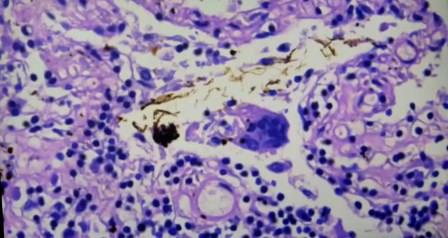

Células gigantes de cuerpo extraño, son como macrófagos en alveolitis

Esta célula gigante en mujer de 80 años

Objetos largos de color marrón que atraviesan la célula en la mayoría de los casos se ha disuelto la parte metálica

Aquí también una parte desprendida en la célula gigante

Así se ve el metal reflejante. Esta partícula tiene un borde muy definido de acero inoxidable en la célula gigante. “Deben haber inyectado en el vaso sanguíneo y no sé si la mujer murió por eso, no tengo todos los datos, pero lo he visto muchísimo, han quitado el requisito de aspirar (con la jeringa)”, al vacunar.